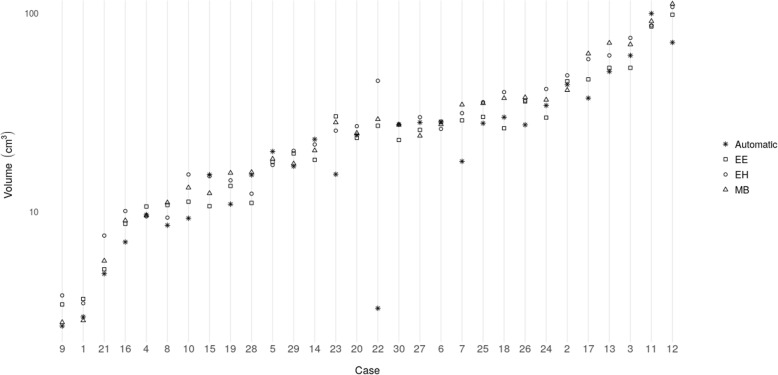

Fig. 2.

Comparison of the automatic approach and the three experts (EE, EH, MB) in terms of Dice coefficient (a), relative volume error (b), and absolute volume (c) on the cross-evaluated cohort. The light gray boxes on the left represent results of automatic method and the dark gray boxes on the right show the experts. P-values indicate the result of the Wilcoxon rank-sum test (α = 0.05) between automatic-rater (Automatic-EE, Automatic-EH, Automatic-MB) and rater-rater (EE-EH, EE-MB, EH-MB) results

Fig. 3.

Comparison of the automatic approach and the three experts (EE, EH, MB) in terms of measured resection cavity volume for each case in the dataset. Note the logarithmic scale of the y-axis

The DC and the relative volume error of the different pairings of expert raters and the automatic segmentation are listed in Table 2. The median overall DC among the raters was 0.85 (interquartile range [IQR]:0.07). The median DC between the automatic segmented RCs and the fused reference segmentation was 0.84 (IQR: 0.10), and slightly lower than the agreement among raters. In terms of relative volume error, we found a median error of − 13.17%, (IQR: 24.17%) between automatic and reference segmentations, which indicates the DL method underestimated the RC with respect to the raters. The median of the absolute volume was 24.7cm3 (IQR: 19.1cm3) for EE, 26.6cm3 (IQR: 26.7cm3) for EH, 26.1cm3 (IQR: 23.3cm3) for MB and 21.7cm3 (IQR: 19.6cm3) for the automatic segmentation. Figure 2 shows boxplots of DC values, relative volume errors and the absolute volumes for the automatic approach in relation to the experts. According to the Kruskal Wallis test we did not detect a statistically significant difference regarding the distribution of the measured volumes for the different raters and the automatic method (chi-square = 1.46, p = 0.69). In contrast, a statistically significant difference in DC (chi-square = 11.63, p = 0.04) and relative volume error (chi-square = 22.45, p = 0.00043) was found. The result of the subsequent Wilcoxon rank-sum test between rater-to-rater (EE-EH, EE-MB, EH-MB) and automatic-to-rater (Automatic-EE, Automatic-EH, Automatic-MB) pools are shown in Figs. 2 and 3. The automatic segmentation volumes tend to be smaller than the expert volumes, which corresponds with the underestimation found in the relative volume error measurement. The main sources of error by the automatic method were localized to signal inhomogeneity (especially in T2w and FLAIR sequences) and other intensity patterns (edema, subarachnoid space, or ventricles). Figure 4 shows cases representing good and bad performances.